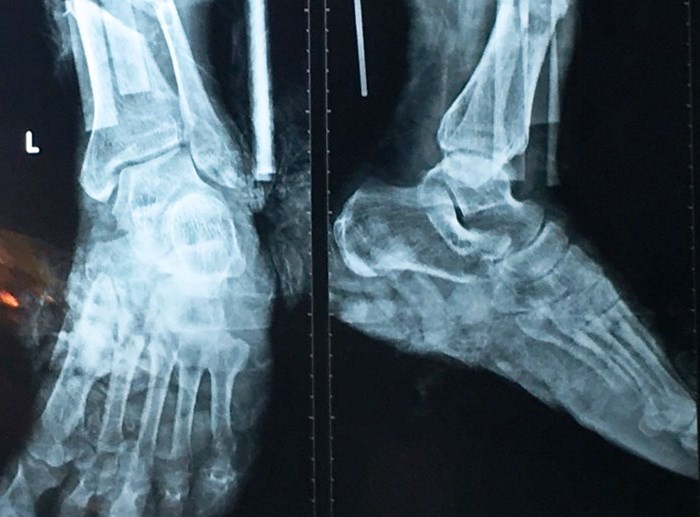

| Hình ảnh chụp X-quang bàn chân của bệnh nhân. Ảnh: Hòa Khánh. |